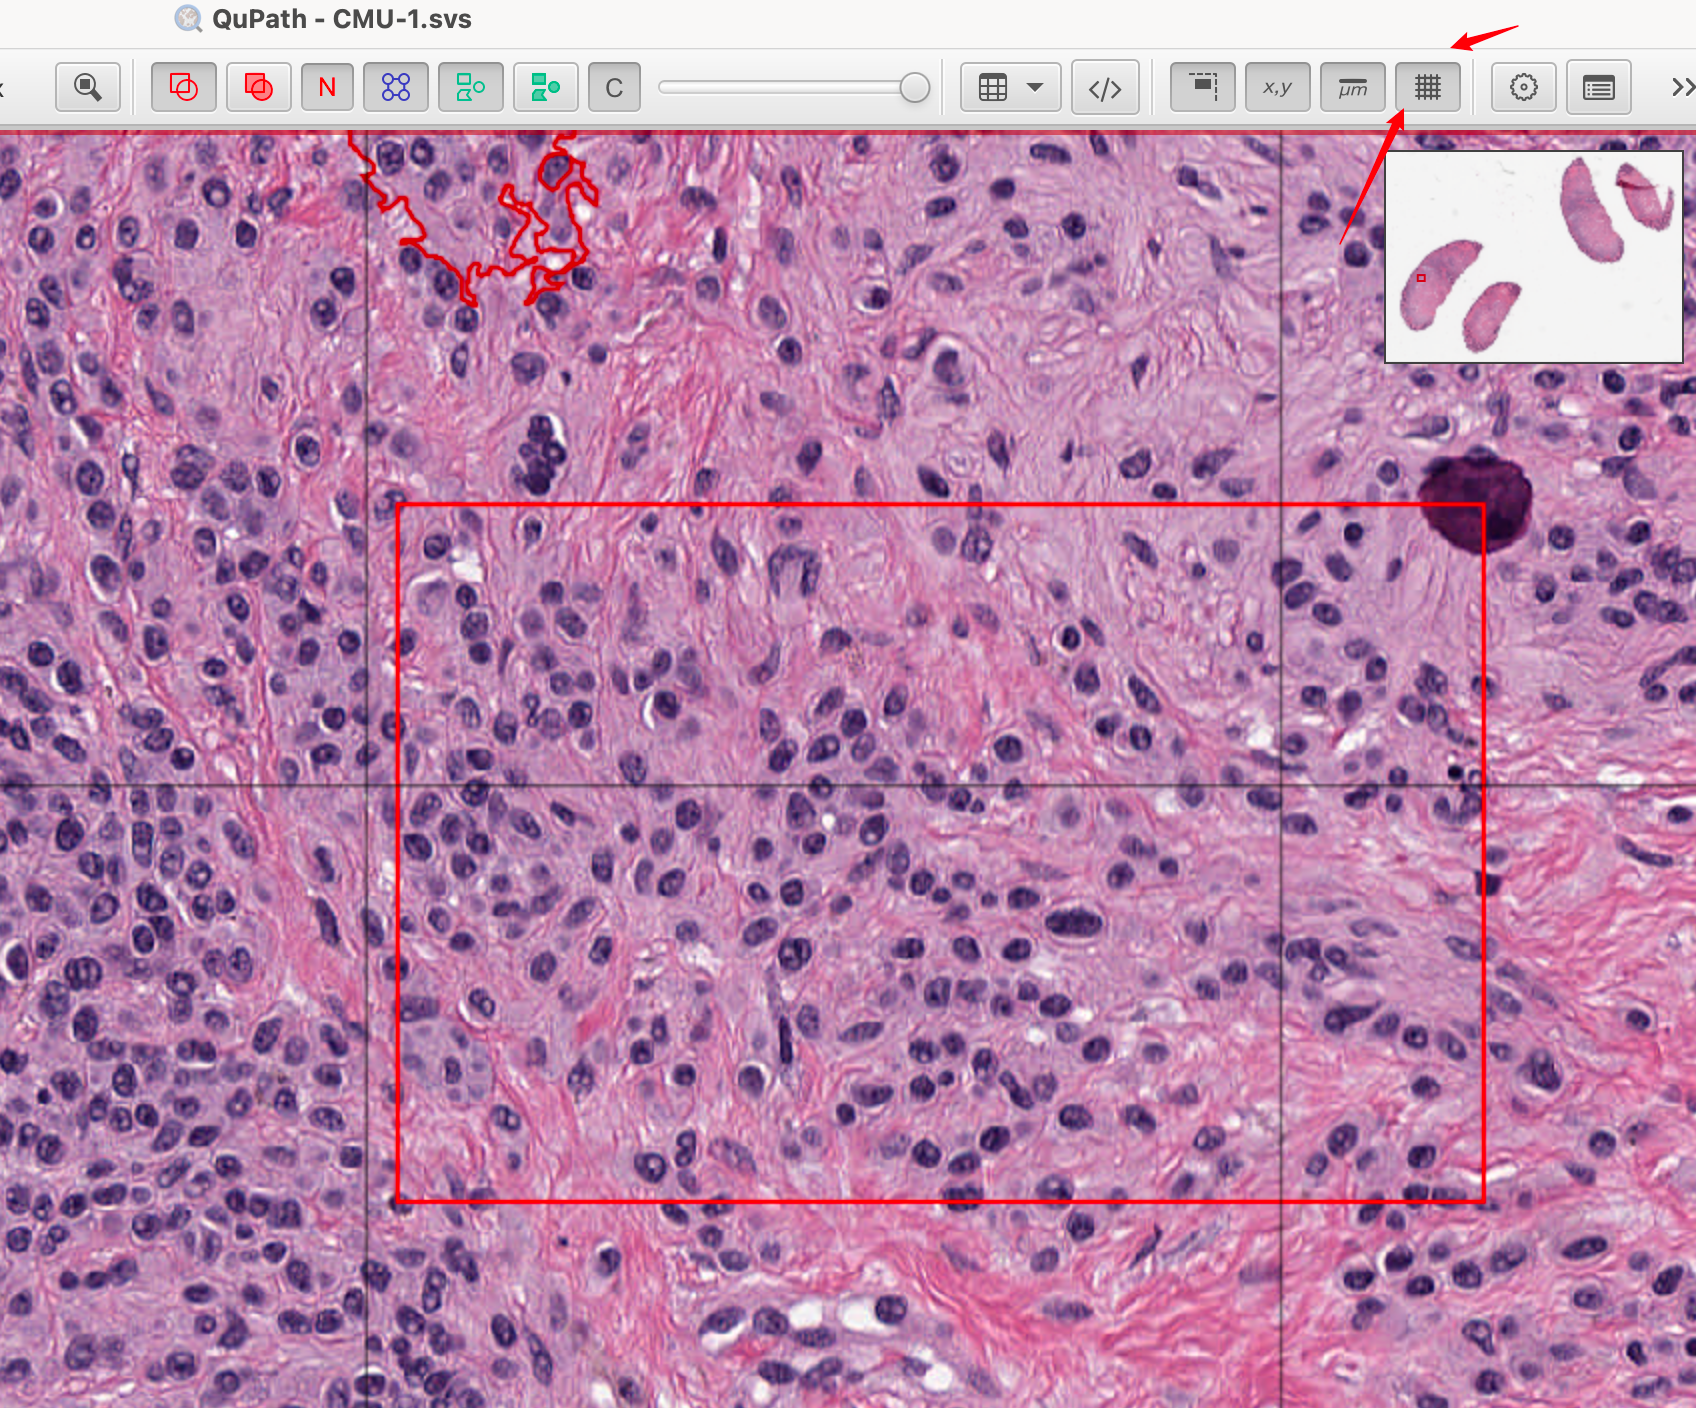

或者,您可以点击右上角的概览图像自动跳转到特定区域。

2-10:显示与隐藏

随着图像上对象数量的增加,可能会变得杂乱或令人困惑。有四个有用的工具栏按钮可以帮助自定义对象如何显示。

这些按钮允许您快速切换显示标记,以在查看分析数据和底层图像之间切换。

完成此操作后,可以选择(但很有帮助)在图像上叠加一个网格,以协助在固定区域进行计数。这可以通过简单地点击显示网格的工具栏按钮来完成。